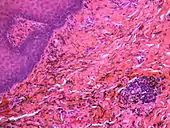

| Amalgam tattoo in upper labial sulcus in an edentulous individual, left behind after teeth have been lost/extracted | |

Amalgam tattoo is a grey, blue or black area of discoloration on the mucous membranes of the mouth, typically on the gums of the lower jaw. It is a healthcare caused lesion, due to entry of dental amalgam into the soft tissues. It is common, painless, and benign, but it can be mistaken for melanoma.

Amalgam tattoo usually occurs on the mandibular gingiva, often in an area in which an apicoectomy ("root-end filling") with amalgam was carried out.[3]: 138 After the gingiva, the alveolar mucosa and the buccal mucosa are the next most common sites, although any mucosal site in the mouth is possible.[1] It is painless, and appears as a blue-black or grey discolored macule on the surface of the mucosa.[3]: 138 [4]: 330 [5]: 183 The borders of the tattoo are variable, and may be well defined, irregular or diffuse.[1]